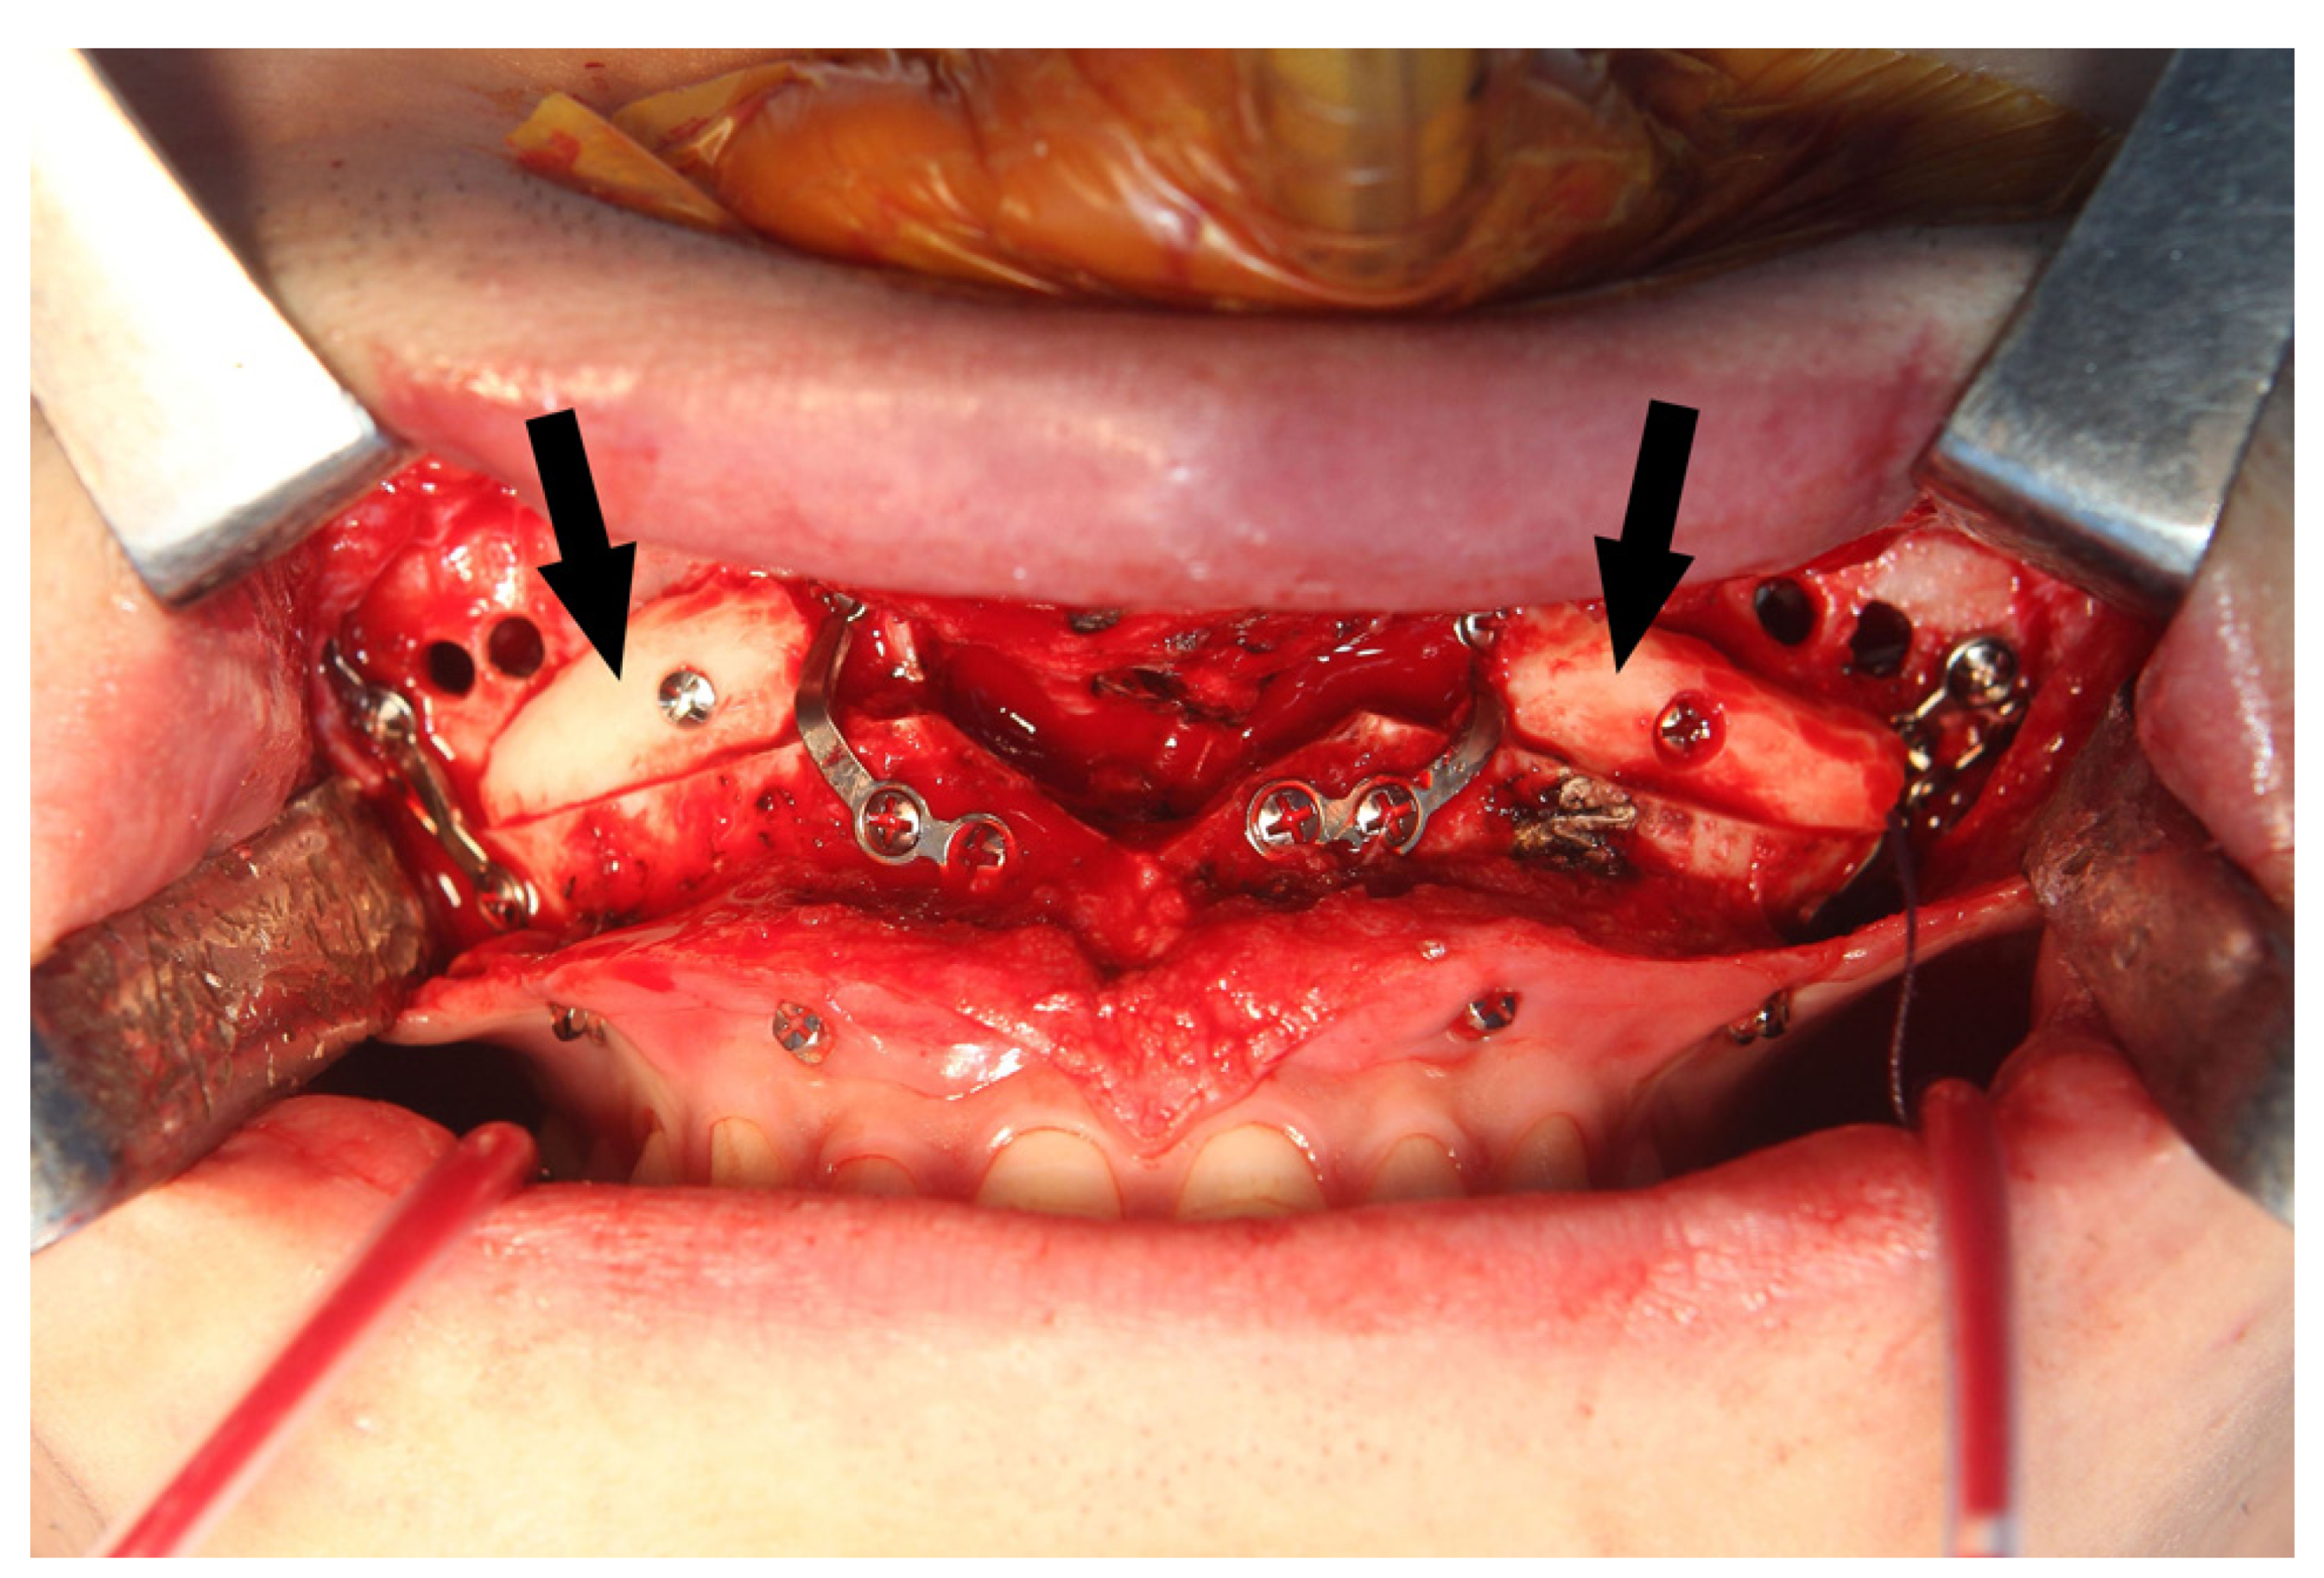

2. Materials and Methods